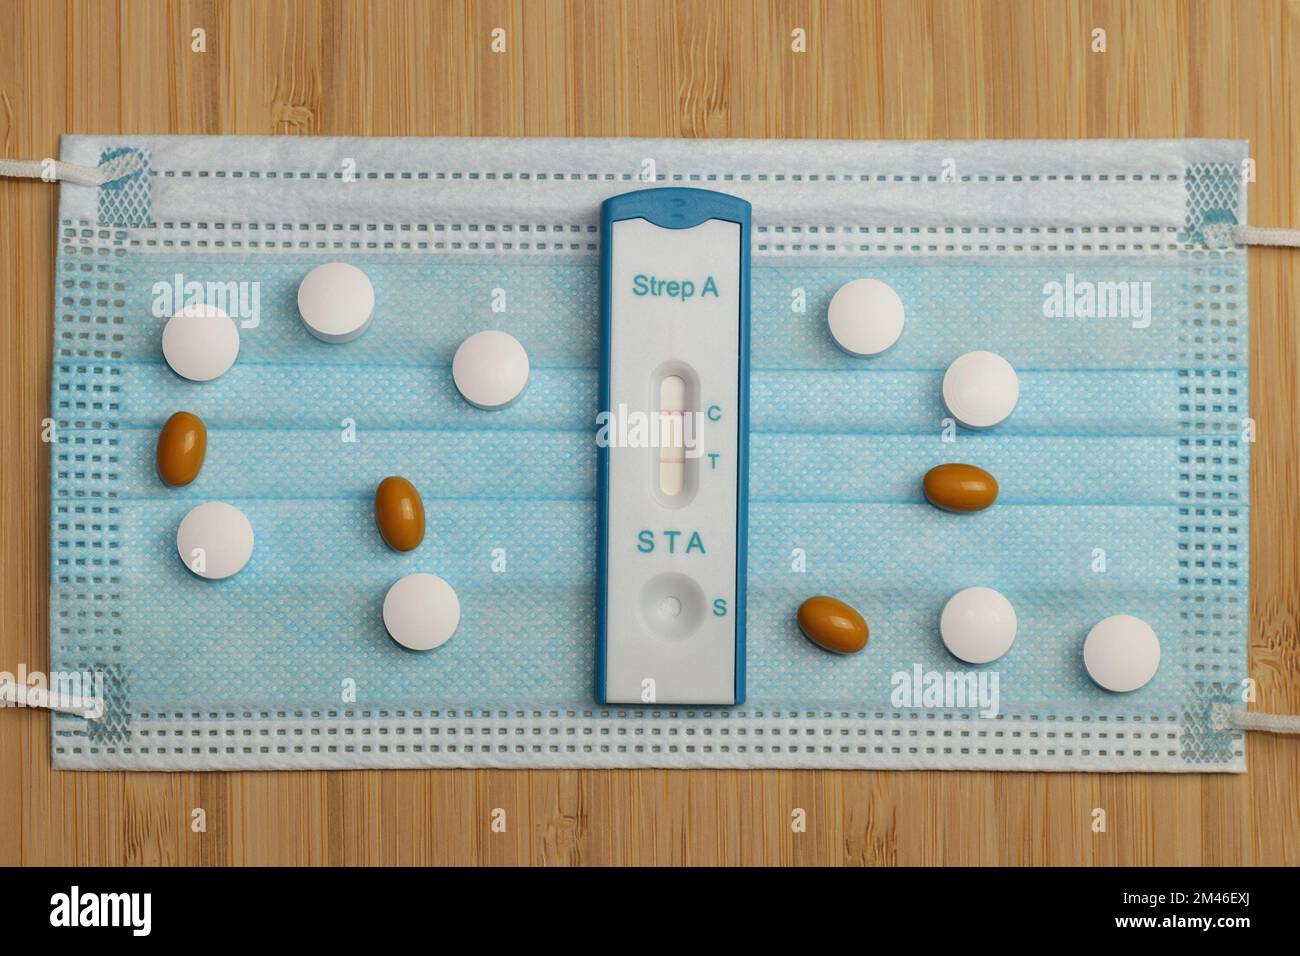

Ein Schnelltest für Streptokokken der Gruppe A mit positivem Ergebnis liegt auf einer chirurgischen Gesichtsmaske. Diese Bakterien verursachen Erkrankungen Tonsillitis und Scharlach. Stockfotohttps://www.alamy.de/image-license-details/?v=1https://www.alamy.de/ein-schnelltest-fur-streptokokken-der-gruppe-a-mit-positivem-ergebnis-liegt-auf-einer-chirurgischen-gesichtsmaske-diese-bakterien-verursachen-erkrankungen-tonsillitis-und-scharlach-image501702730.html

Ein Schnelltest für Streptokokken der Gruppe A mit positivem Ergebnis liegt auf einer chirurgischen Gesichtsmaske. Diese Bakterien verursachen Erkrankungen Tonsillitis und Scharlach. Stockfotohttps://www.alamy.de/image-license-details/?v=1https://www.alamy.de/ein-schnelltest-fur-streptokokken-der-gruppe-a-mit-positivem-ergebnis-liegt-auf-einer-chirurgischen-gesichtsmaske-diese-bakterien-verursachen-erkrankungen-tonsillitis-und-scharlach-image501702730.htmlRF2M46EXJ–Ein Schnelltest für Streptokokken der Gruppe A mit positivem Ergebnis liegt auf einer chirurgischen Gesichtsmaske. Diese Bakterien verursachen Erkrankungen Tonsillitis und Scharlach.